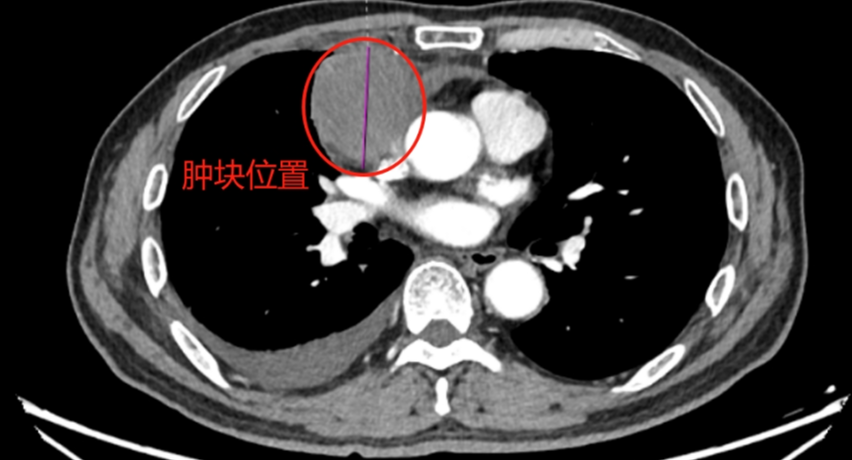

警惕!64岁男子胸口反复胀痛,竟是“秋月梨”大小的肿瘤作怪!

健康 纵隔肿瘤

湖南医聊 2025-08-15